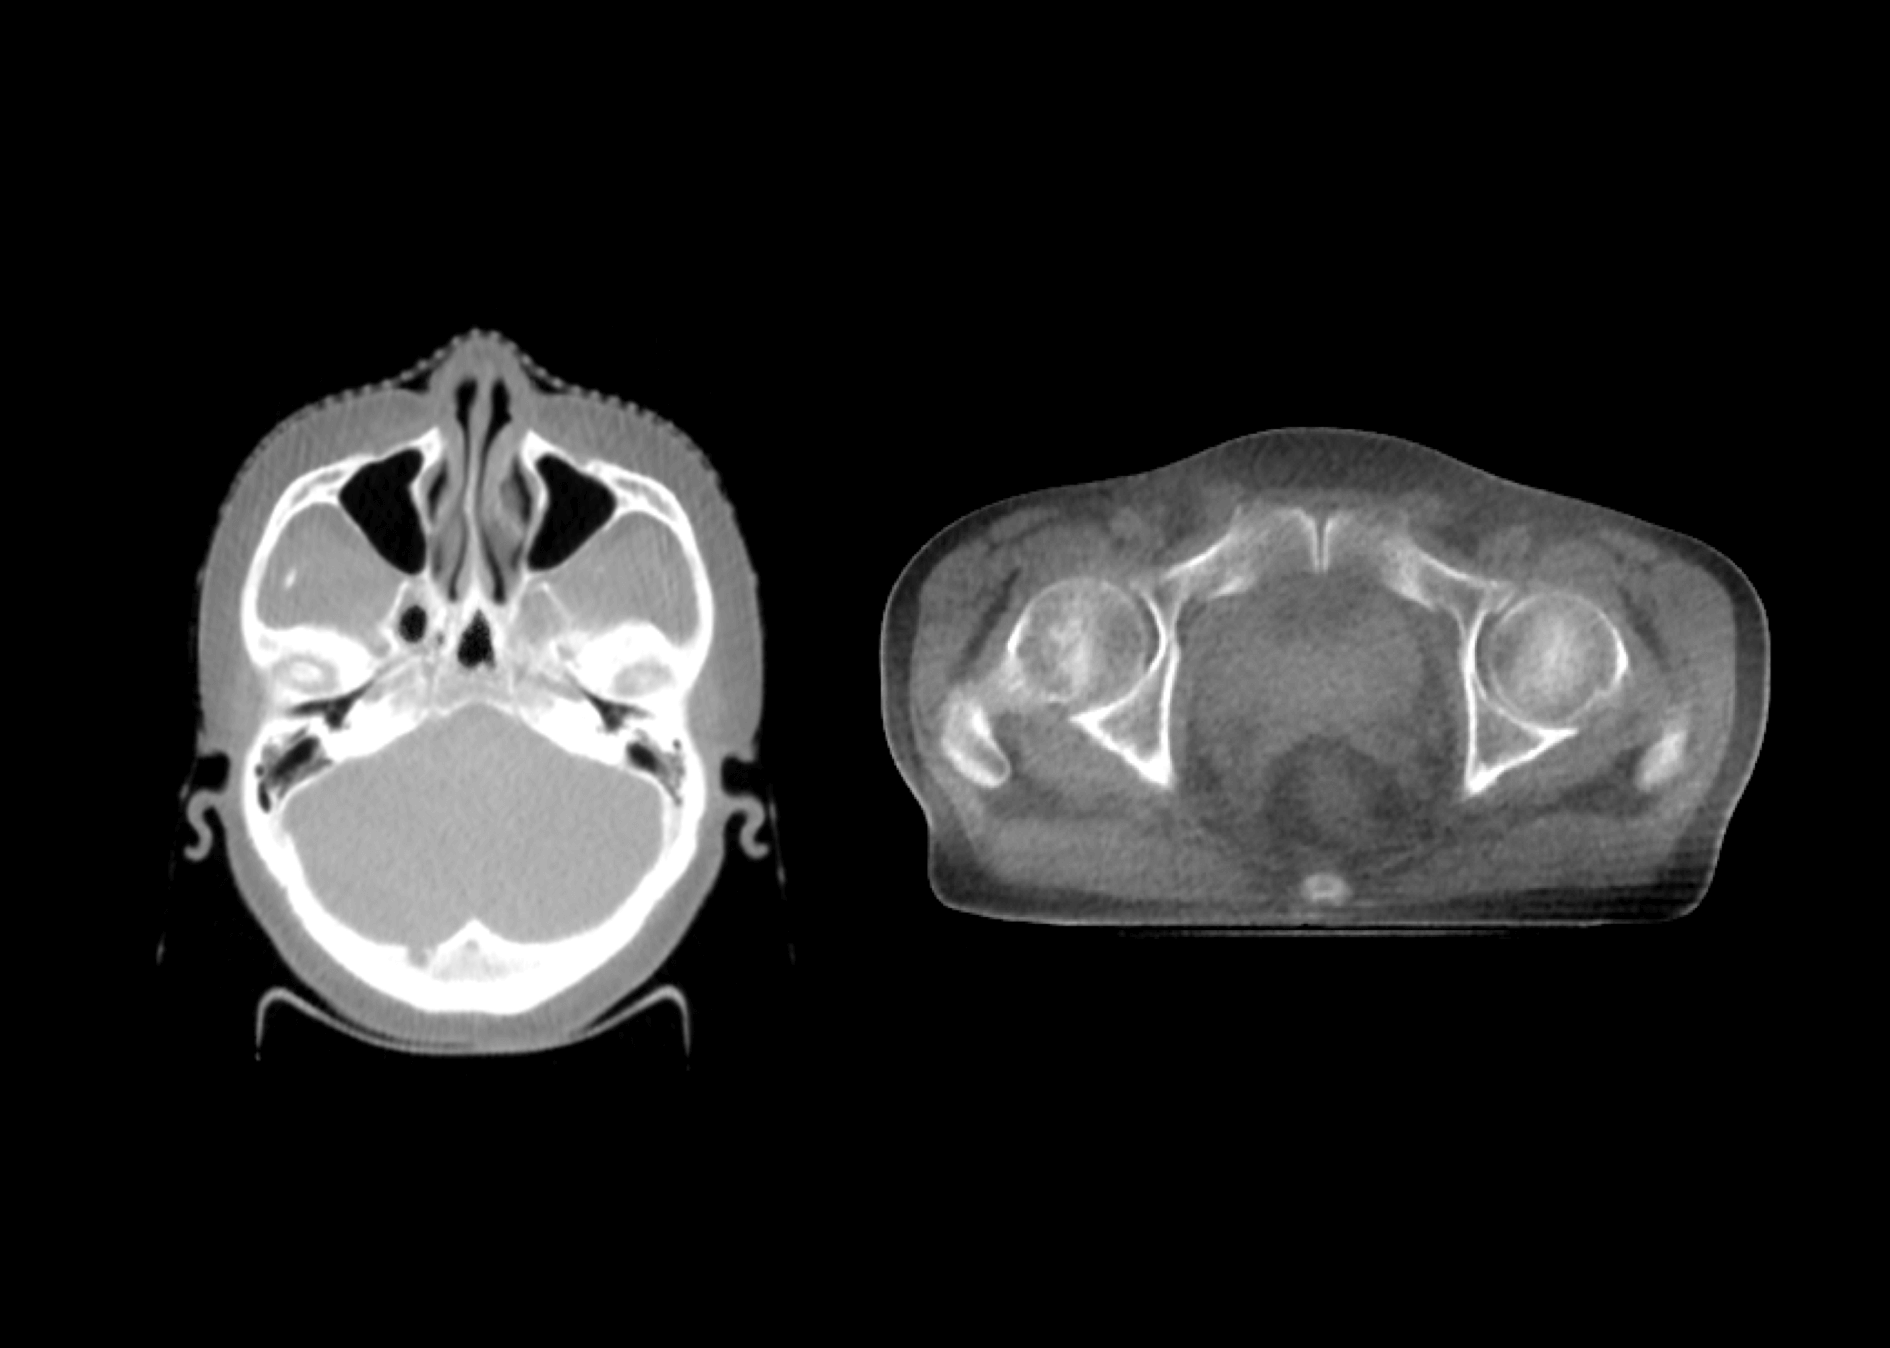

成就类kV级CBCT成像

深度调能成像技术

1.5MeV电子束打靶,使得千伏级成像光子占比更大,图像质量媲美常规kV级CBCT。

影像引导成像束流与治疗束流同一等中心,带来更高的图像引导精度。

一键CBCT成像,自动配准,自动移床,自动避撞,高度自动化,有效提升效率。